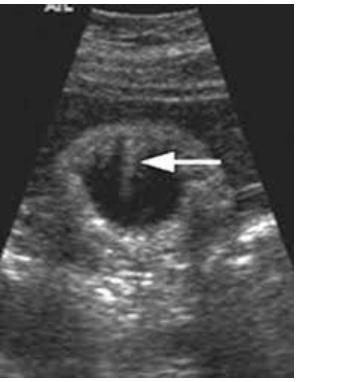

WHat pathology is found below ?

Adenomyomatosis - Small echogenic foci at abdominal wall, comet tai